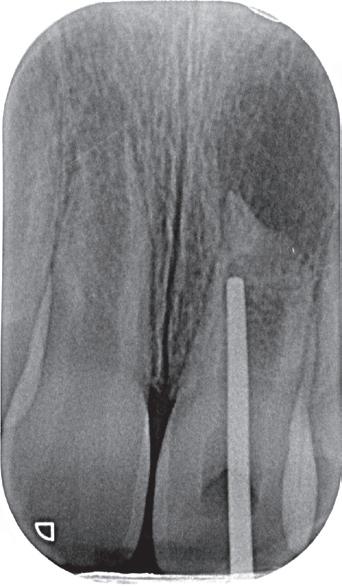

Trauma bij een 11-jarige. Tand 41 was geluxeerd met een beperkte extrusie. Hij reageerde niet op koude en de vraag was om een wortelkanaalbehandeling uit te voeren (foto 4). Bij trauma wordt er echter dikwijls te snel een conclusie getrokken en aangezien er geen

klinische klachten waren, werd besloten om verder op te volgen. Acht maanden later reageren alle tanden vitaal en is tand 41 aan het verkalken. Er is dus geen wortelkanaalbehandeling nodig (foto 5).